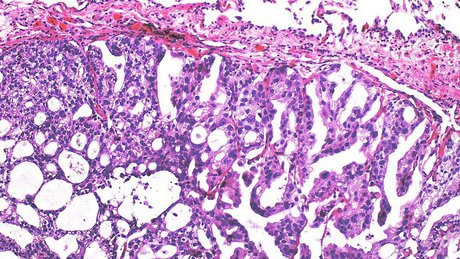

مهراد با اشاره به انواع بیماری‌های پروستات ابزار داشت: پروستات چند نوع بیماری دارد؛ یکی بزرگی خوش‌خیم پروستات است و نوع دوم سرطان پروستاتیک بوده که از شایع‌ترین سرطان‌های مربوط به آقایان در دنیا است اما می‌توان با یک آزمایش آن را غربالگری کنیم.